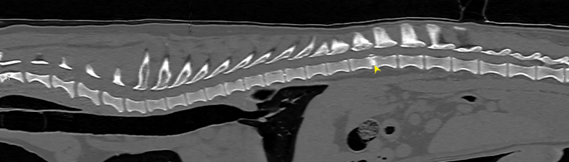

臘腸狗狗 椎間盤疾病 ivdd

懷疑椎間盤疾病的狗狗 常見背痛、腳無力、癱瘓,需要由專業的獸醫師神經學檢查

評估定位病灶區域 搭配電腦斷層掃描來決定手術位置及手術方式